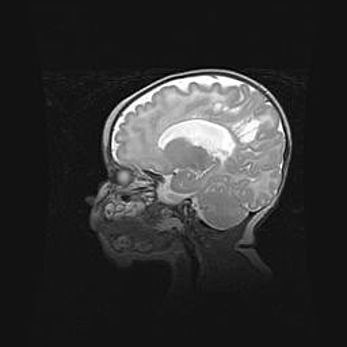

Мальформация Денди-Уокера. Киста задней черепной ямки.

Агенезия мозолистого тела.

Возраст: 2,5 месяца

Вес: 2420 г

Пол: женский

Окружность головы: 37 см

Срок гестации: 32 недели

Мальформация Денди—Уокера — редкий вид патологии ЦНС, представляющий собой врожденный порок развития каудального отдела ствола и червя мозжечка, ведущий к неполному раскрытию срединной (Мажанди) и латеральных (Лушка) апертур IV желудочка мозга. Для этогно синдрома характерна триада симптомов: гипотрофия червя мозжечка и/или полушарий мозжечка, кисты задней черепной ямки, гидроцефалия различной степени. В 70% случаев порок сочетается и с другими аномалиями головного мозга, в частности с агенезией мозолистого тела.